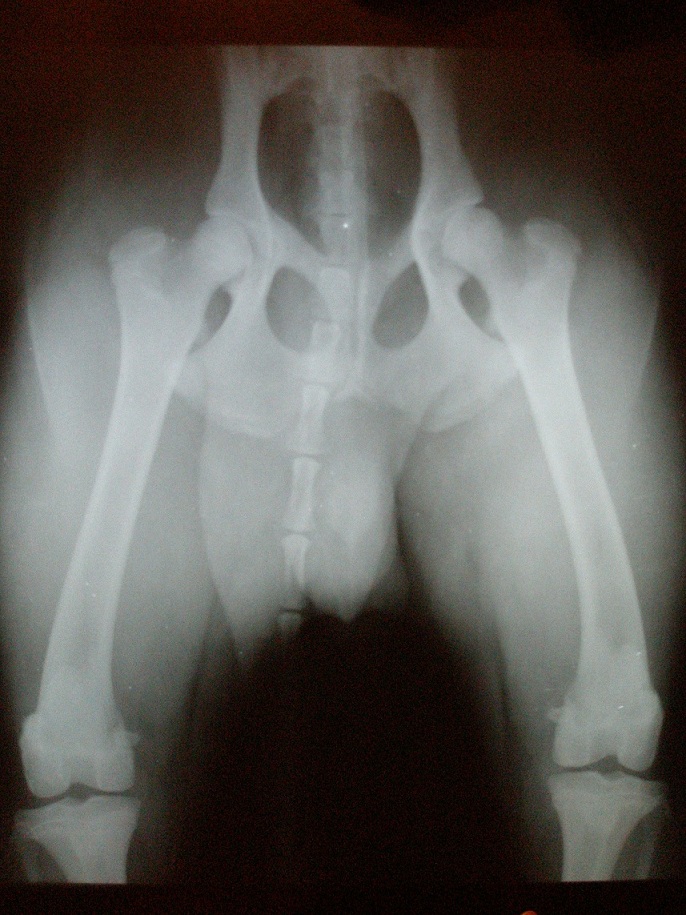

Это тяжелый случай двусторонней дисплазии тазобедренного сустава

Это тяжелая дисплазия тазобедренного сустава

Собаки — не единственный вид, у которого наблюдается дисплазия тазобедренного сустава. Это также может произойти у кошек, хотя и не так часто, как у собак. Мейн-куны — это порода кошек, которая чаще всего поражается.

Пожилая кошка с дисплазией тазобедренного сустава